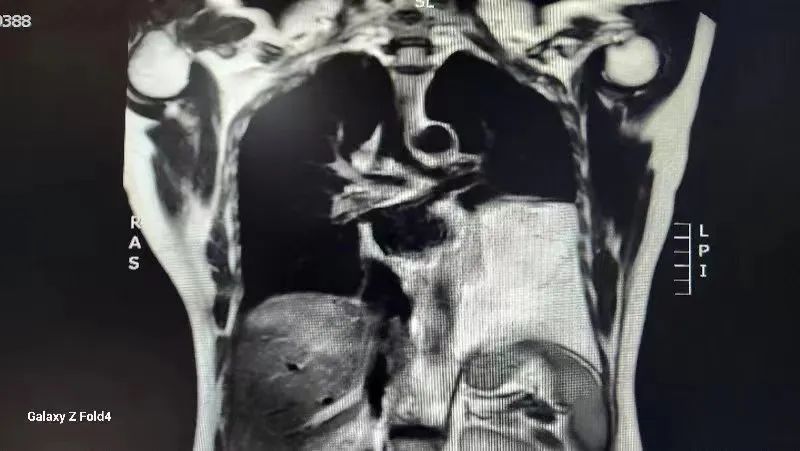

入住市中心医院胸外科后,胸CT检查示纵膈内心包左侧见团状脂肪密度影,较大层面大小约9.7*14.2厘米。完善纵隔磁共振等相关检查,根据检查结果高度怀疑纵膈内脂肪肉瘤。